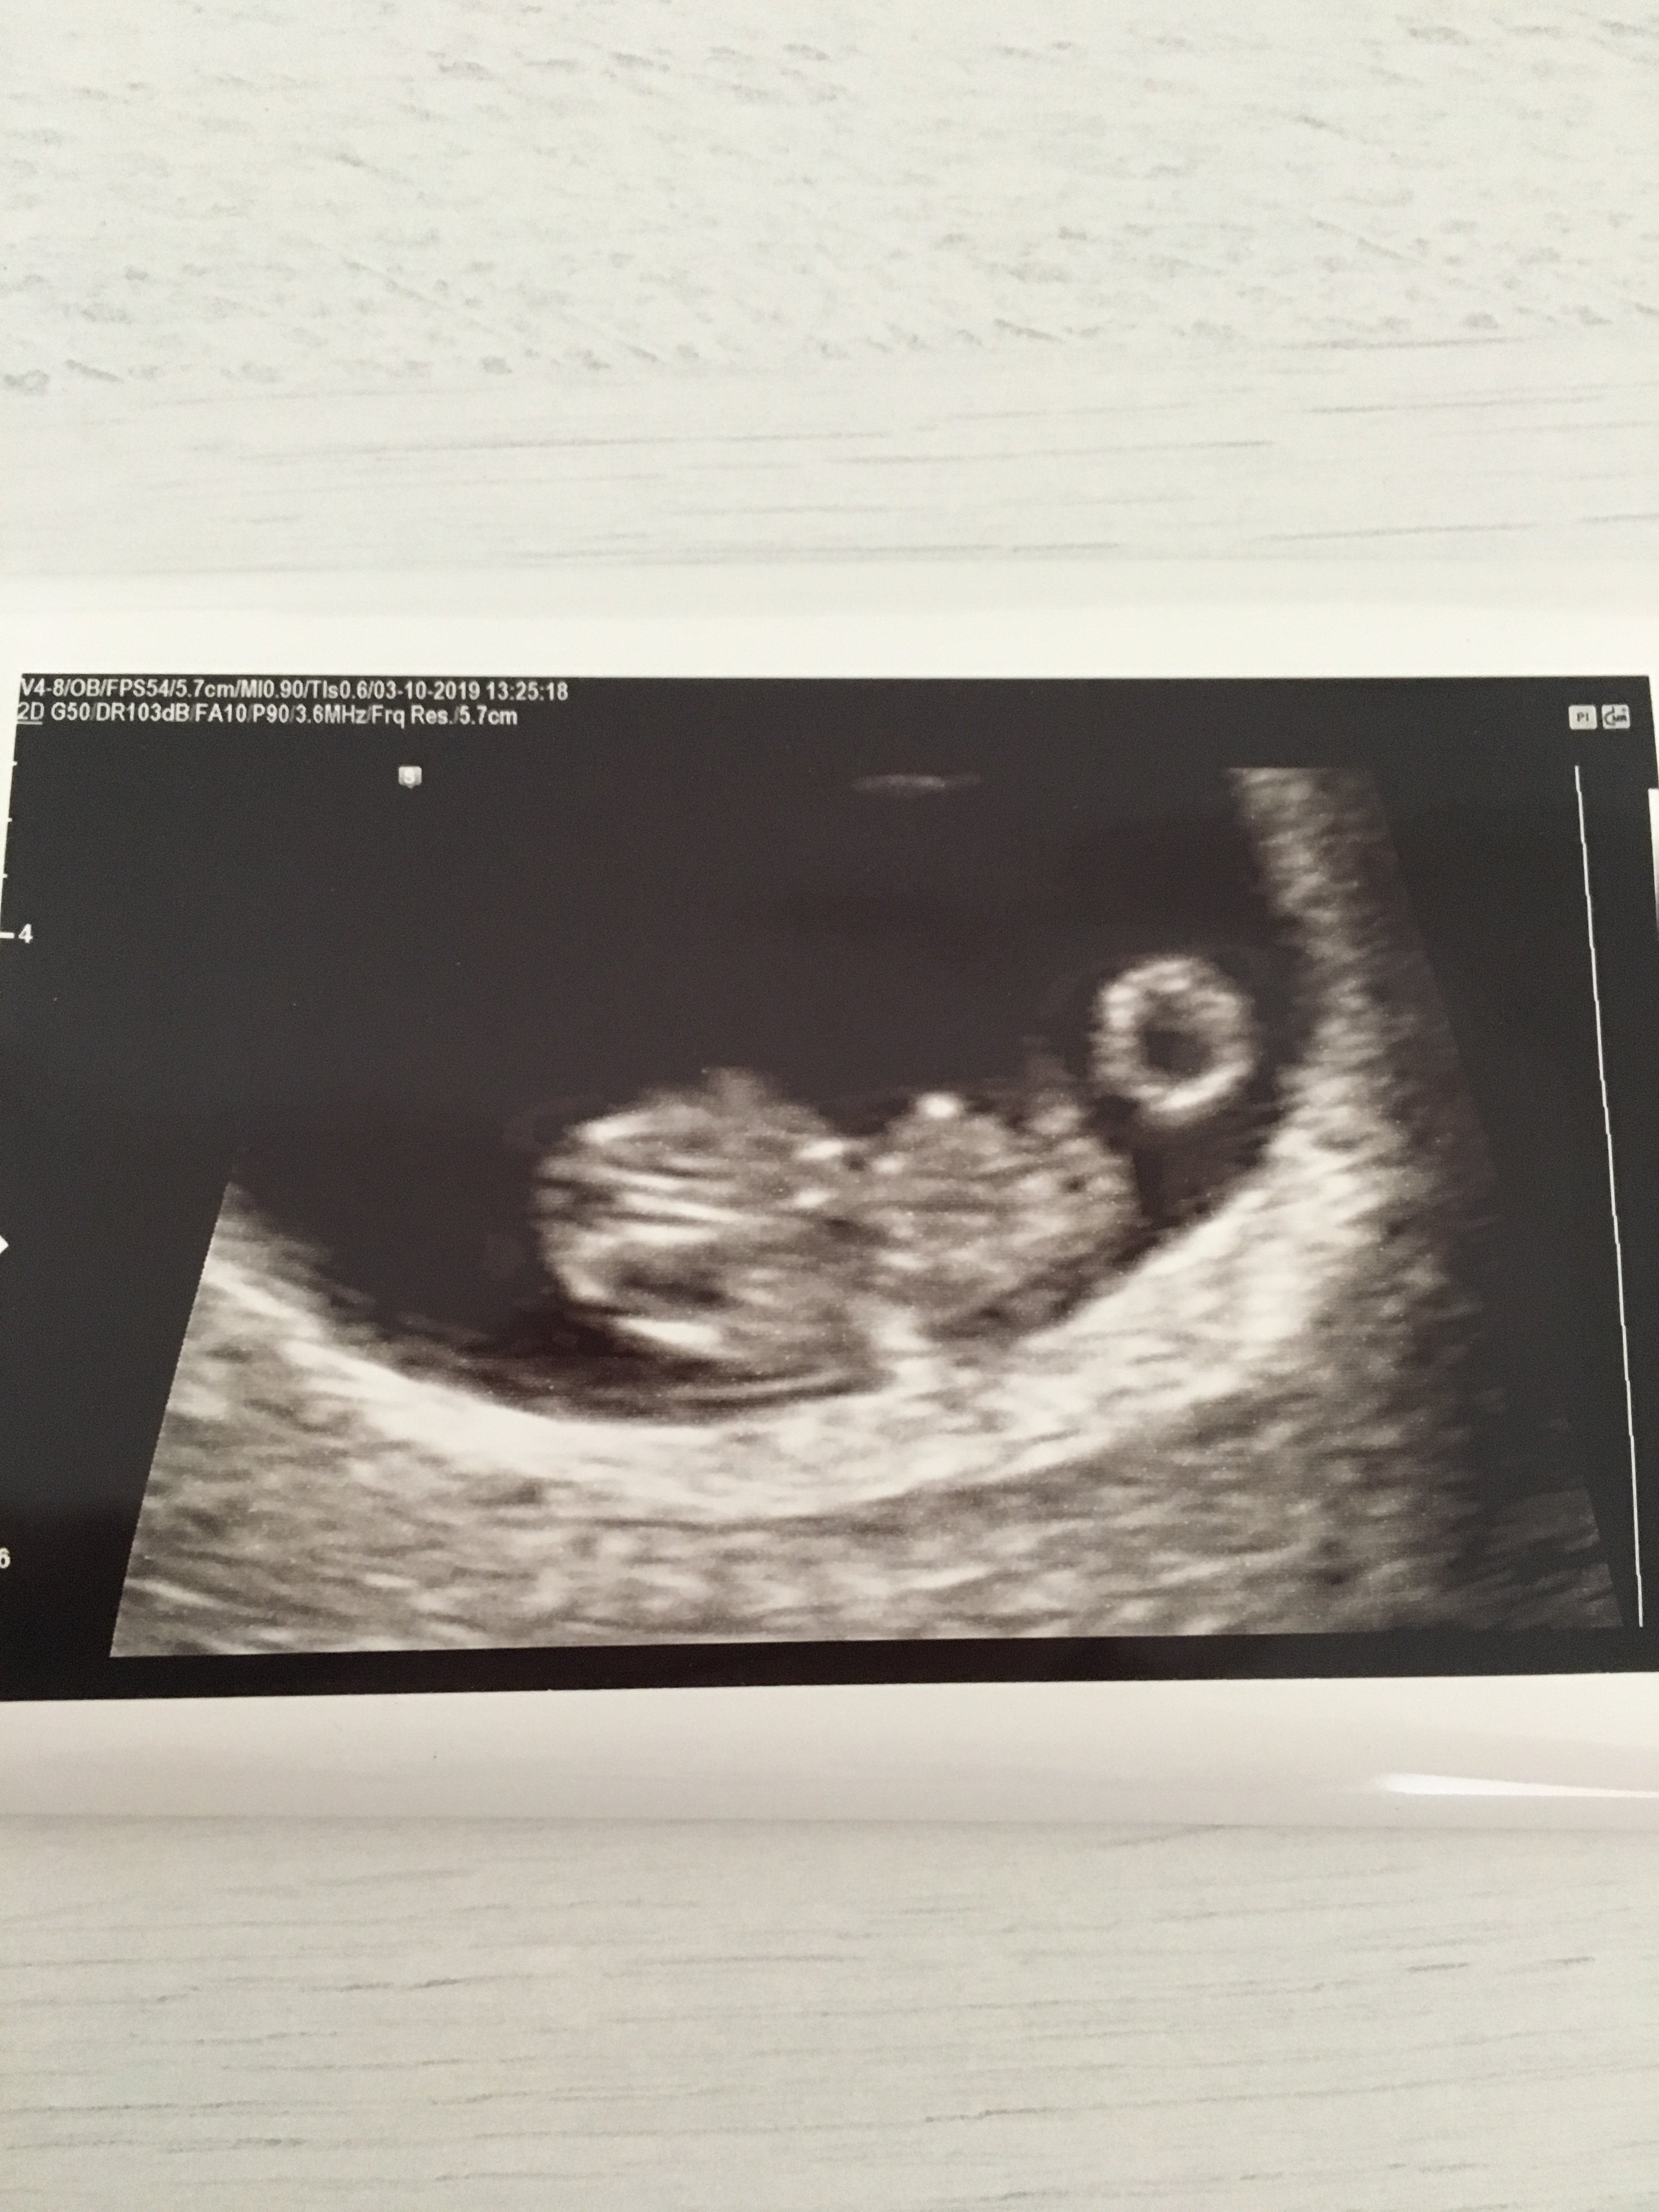

Ja już po usg i wszystko jest w porządku. Jedno maleństwo - 2cm 8-) o jakiś tydzień starsze niż wg OM. Słyszałam serduszko, coś pięknego :):):) Kolejne usg za 3 tygodnie w 12 tygodniu.

Zobacz załącznik 1029642